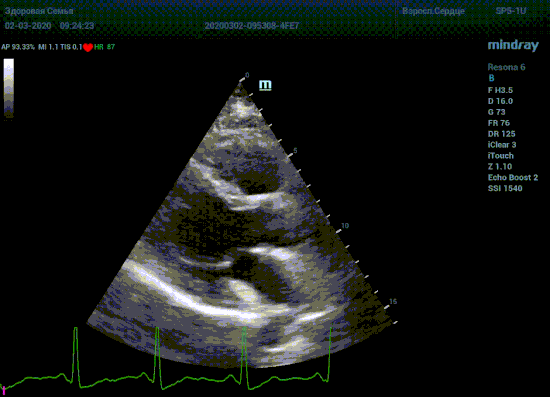

Терапия наиболее широкая область применения, однако взрослая кардиохирургия так же важное направление современной медицины. Оперировать аортальный стеноз, или же площадь клапана достаточная? Необходимо рассчитать площадь аортального клапана по уравнению непрерывности потока. Для этого нужно измерить на зуме выносящий тракт левого желудочка (LVOT) в середине систолы. Будем угадывать момент или возьмем середину Т зубца по ЭКГ? Доверимся интуиции при определении показаний к оперативному лечению или науке?

Детская кардиохирургия не исключение. Наиболее актуальная проблема — это дефекты межпредсердной и межжелудочковой перегородок, а также открытый артериальный проток. Не верная оценка гемодинамической значимости приведет к перегрузке правых отделов сердца и ряду осложнений, в случае если не прооперировать вовремя. Отправлять маленького ребенка под нож или подождать пока дефект перегородки зарастет сам? Ждем осложнений или ждать безопасно? На эти вопросы ответит Qp/Qs соотношение, рассчитанное методом эхокардиографии. Для этого необходимо рассчитать ударные объемы выносящих трактов желудочков, опять же на середине систолы – середине Т–зубца ЭКГ.